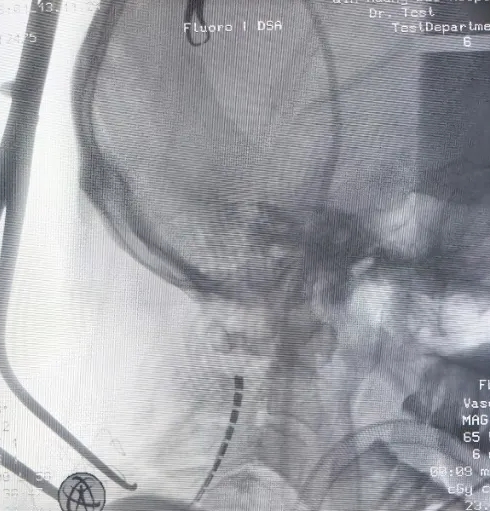

X线电极

详细的手术计划是治疗成功的根本。手术采取分期进行的方式:一期进行临时电极植入,二期进行永久电极植入。并顺利按计划实施治疗。